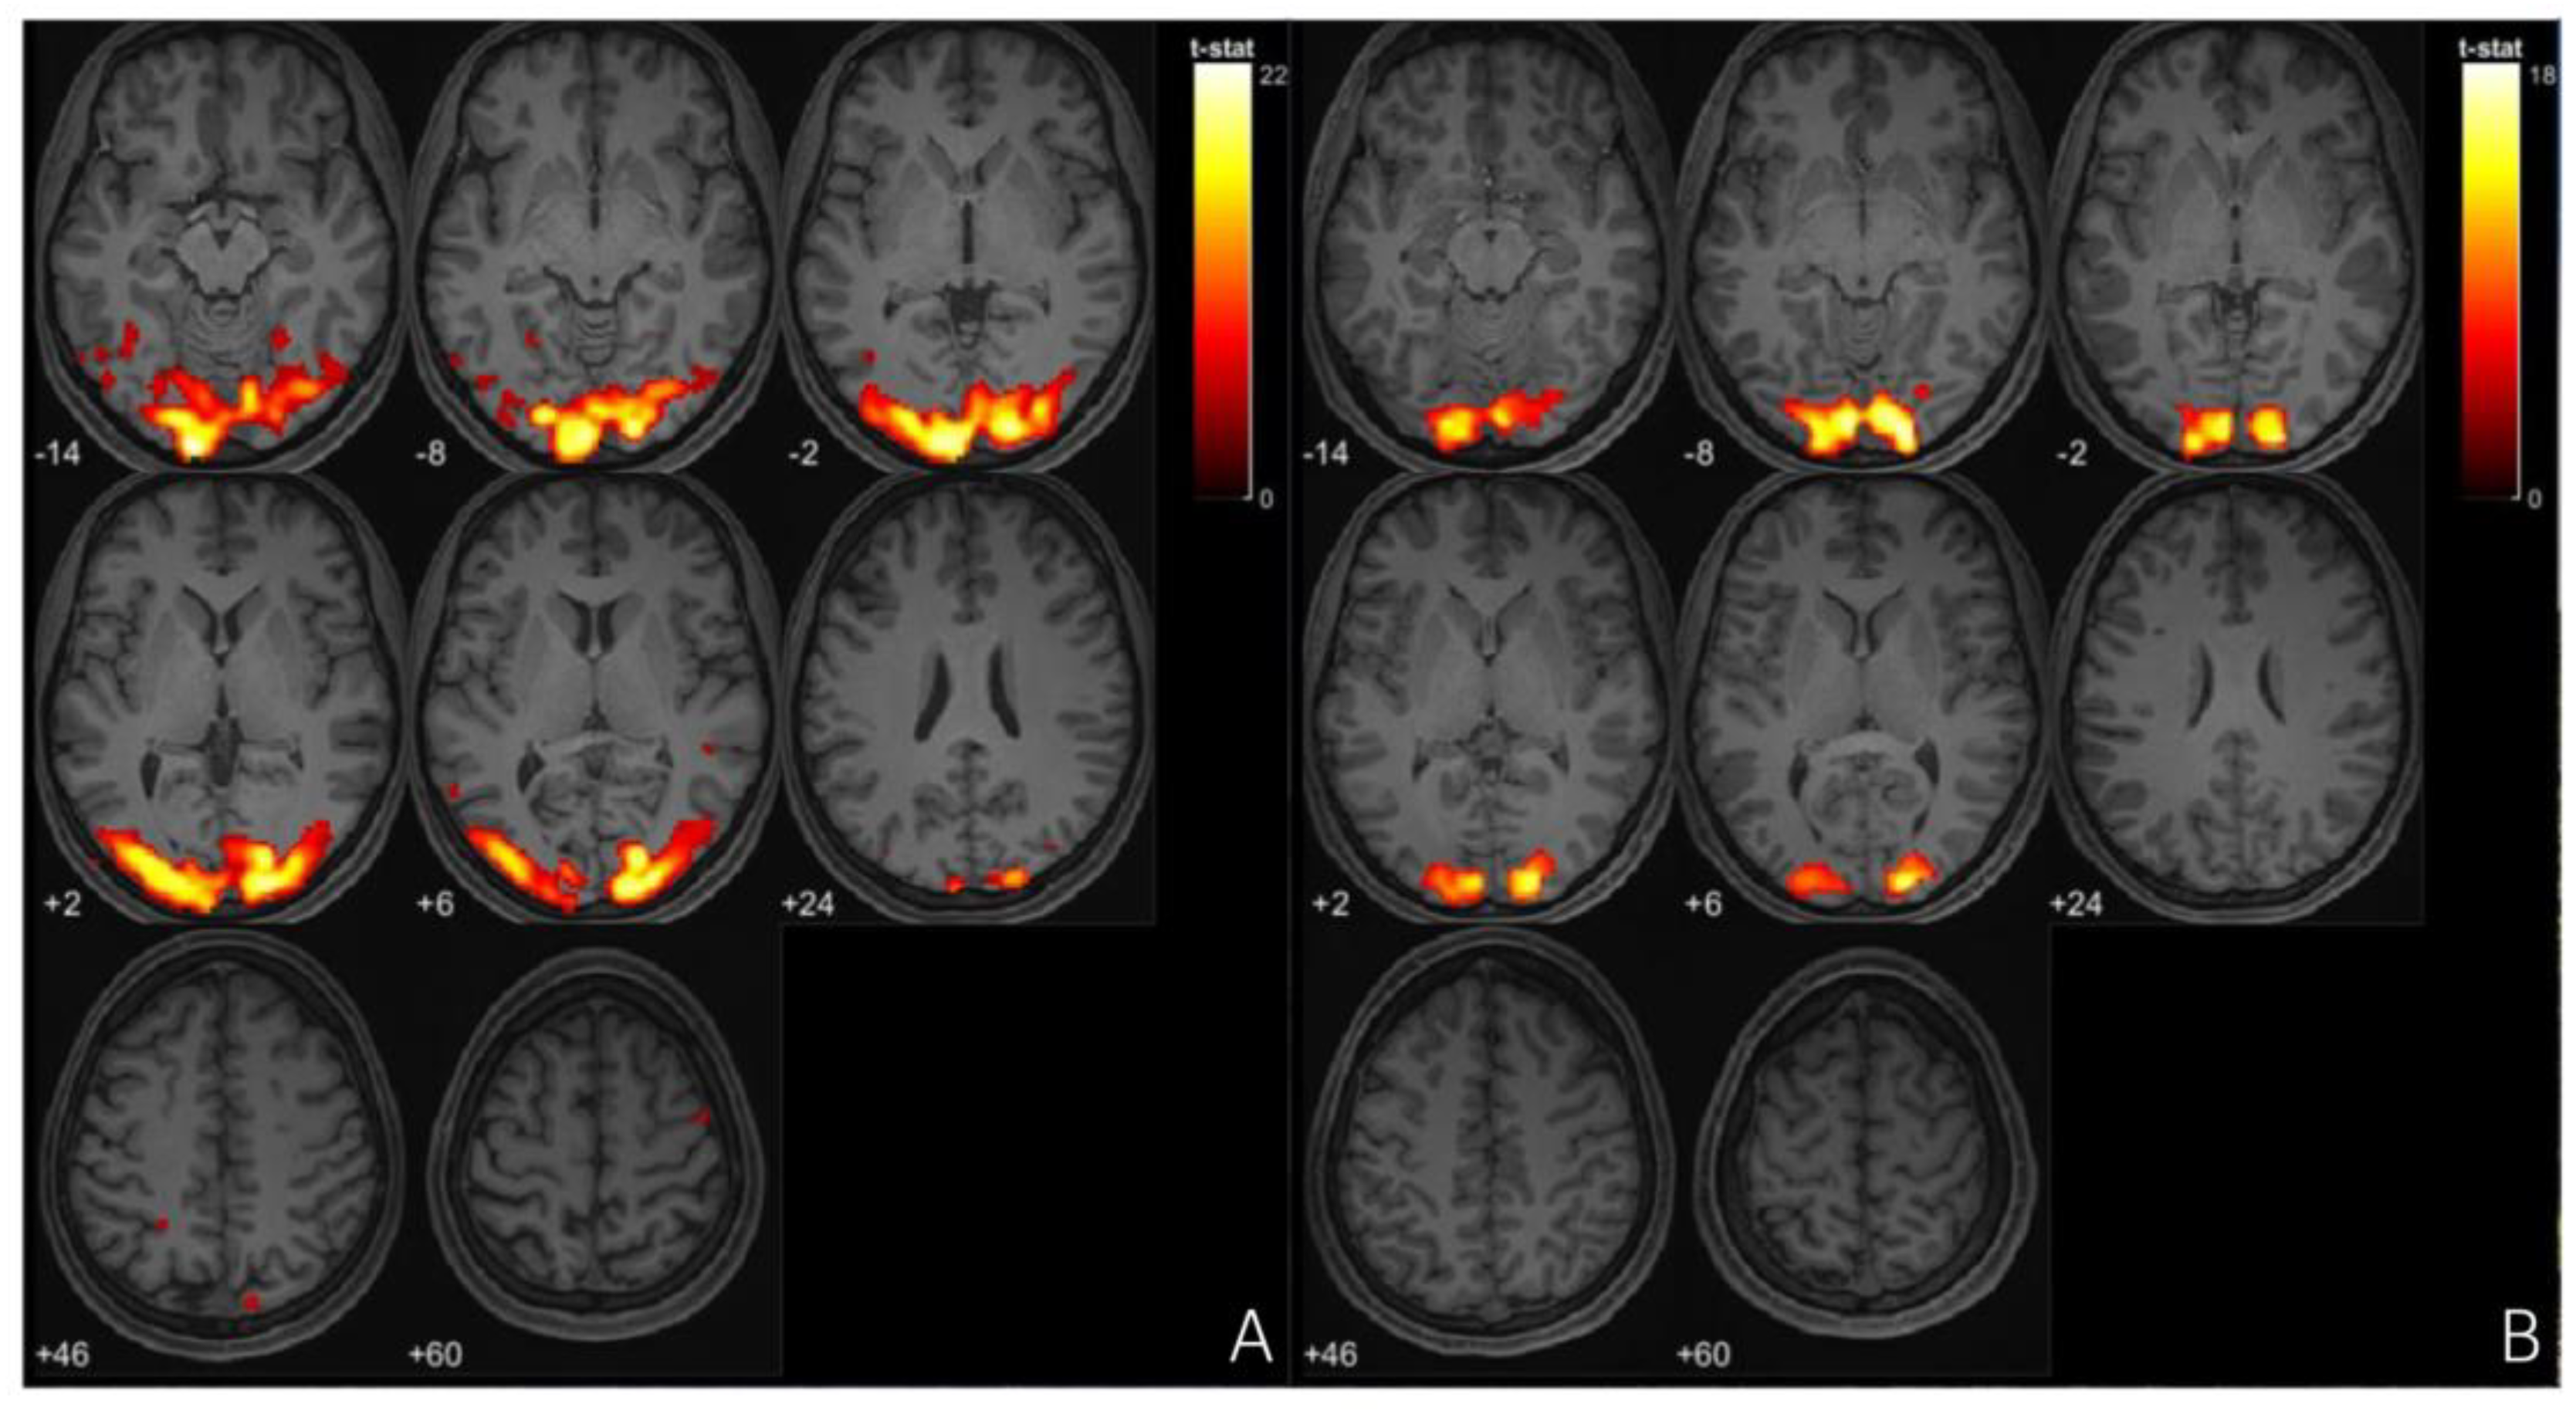

Functional MRI (fMRI) studies of migraine with aura (MA) have identified distinct neural alterations, particularly in resting-state functional connectivity (rs-FC). Increased rs-FC is observed in regions such as the occipital cortex, sensorimotor networks, and visual areas like the lingual gyrus, which play a critical role during both ictal and interictal phases of MA [97,98], [Figure 3 and Figure 4]. Altered connectivity is also found in the thalamus, insula, and cingulate cortex, suggesting the involvement of key pain-processing networks [99]. Furthermore, differences in rs-FC between MA and migraine without aura (MwoA) point to potential biomarkers distinguishing these subtypes [100]. These findings support the notion that distinct neural circuits may underlie the different clinical presentations of migraine, offering new insights into the pathophysiology of the disorder. In tension-type headache (TTH), fMRI studies highlight distinct neural changes that may offer insight into the underlying mechanisms of the condition. Increased fractional amplitude of low-frequency fluctuations (fALFF) is observed in the right posterior and anterior insula in episodic TTH patients compared to healthy controls, while reduced fALFF is found in the posterior cingulate cortex [101]. ReHo analysis reveals increased activity in the right medial superior frontal gyrus [102], though other studies report decreased ReHo in regions such as the bilateral caudate nucleus and frontal gyri [103]. These findings suggest a disrupted balance of activity across key pain and sensory processing regions, providing a better understanding of TTH’s neural basis and potential therapeutic targets. In trigeminal autonomic cephalalgia (TAC), including cluster headache (CH), fMRI studies have documented altered functional connectivity and brain activation patterns. In CH, increased rs-FC is noted between the hypothalamus and regions such as the pregenual anterior cingulate cortex, visual cortex, thalamus, and right insula [104]. Decreased FC is observed in the right frontal pole and right amygdala in chronic CH patients [105]. These altered connectivity patterns suggest that disruptions in both the sensory and emotional processing circuits contribute to the intensity of pain in CH. Additionally, TAC subtypes like short-lasting unilateral neuralgiform headache attacks with conjunctival injection and tearing (SUNCT) exhibit activation in the posterior hypothalamus, brainstem, and frontal cortices during attacks [106,107,108]. This indicates a significant involvement of the hypothalamus and brainstem in the pathophysiology of TAC. In the case of other primary headaches, such as new daily persistent headache (NDPH), fMRI studies have shown abnormal functional connectivity in brain regions involved in emotion and pain regulation [109]. These abnormalities suggest that NDPH may involve disrupted integration between pain processing and emotional regulation networks. Additionally, structural changes, including alterations in cortical area and grey matter volume, have been reported in NDPH patients [110]. These structural findings further emphasize the chronic nature of NDPH and its potential link to persistent alterations in brain structure and function. These findings underscore the complex neural mechanisms underlying these various headache disorders, suggesting that personalized treatment strategies targeting these neural alterations may hold promise for more effective management.

Figure 3. (A) fMRl imaging of occipital cortex of patient with migraine during aura episode, cluster size- 8068voxels, (B) fMRl imaging of occipital cortex of patient with tension type headaches, cluster size- 2595 voxels.